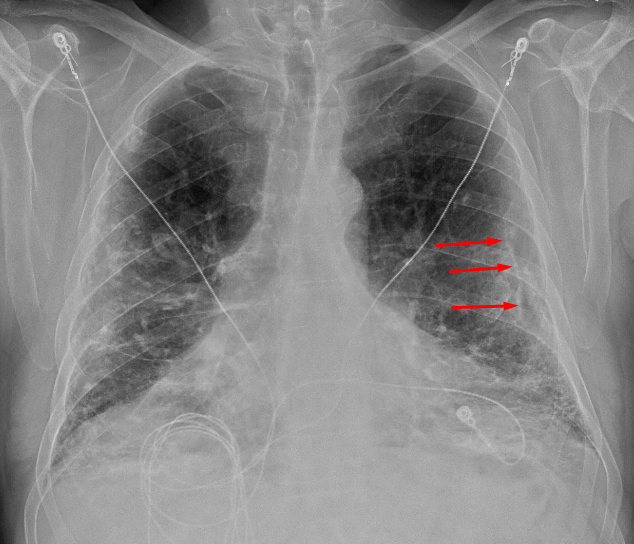

Age: 83

Sex: Male

Indication: Pre-op

Sample ReportBilateral pleural plaques and interstitial coarsening, most prominent at the lung bases. Findings are most suggestive of asbestosis. Consider chest CT for further evaluation.

No definite superimposed focal airspace disease.

Mild cardiomegaly.